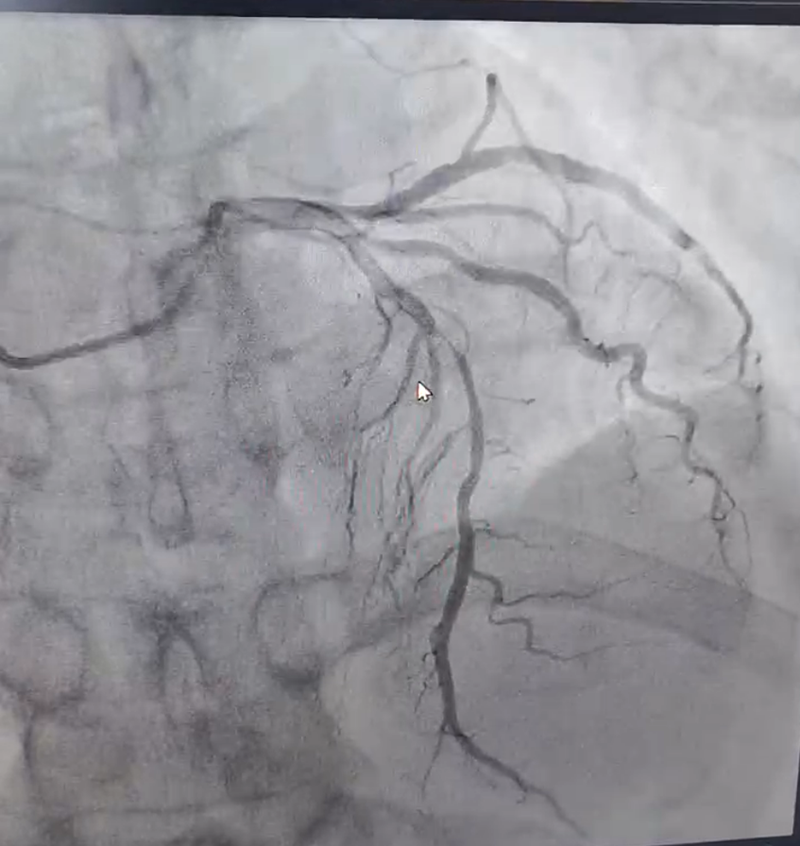

1:急診造影提示前降支中段次全閉塞